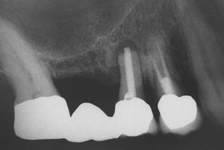

Při ztrátě molárů a premolárů v horní čelisti a jejich náhradě implantáty se často setkáváme s nedostatečnou vertikální nabídkou kosti pod čelistní dutinou, často doprovázenou i nedostatečnou horizontální nabídkou a sníženou kvalitou kosti

(v oblasti 2. premoláru v 50%, v oblasti moláru až v 80% případů nedostatečná kostní nabídka)

Od roku 1985 je tento problém řešen augmentační operací nazývanou sinus lift.

Jedná se o vyzvednutí membrány, která čelistní dutinu vystýlá, pod vyzvednutou membránou vznikne kapsa, kam se umístí augmentační materiál, do kterého se zavedou implantáty.